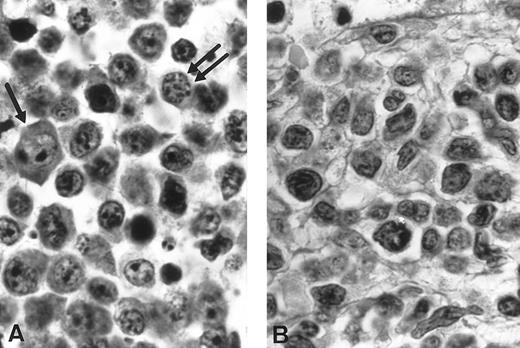

In the third case, the cervical lymph node imprints showed medium and large lymphoid cells. The nuclei exhibited a finely clumped chromatin. The basophilic cytoplasm was relatively abundant with some vacuoles and small azurophilic granules. Mitoses were frequently observed (Fig 1A). Histopathologic study of the lymph node showed a diffuse infiltrate with a starry sky pattern caused by numerous disseminated histiocytes with tingible bodies (Fig 3A). The lymphomatous cells were medium sized, with either an irregular or a more round nucleus with a basophilic cytoplasm. The lymphoma was classified as a high grade pleomorphic T-cell malignant lymphoma with large cell predominance. (Fig 3B). The bone marrow biopsy disclosed a diffuse massive infiltrate constituted by the same cells without myelofibrosis.

Histological findings (Case 3). (A) Diffuse infiltration, high-grade pleomorphic T-cell lymphomas of medium-sized cell predominance with numerous histiocytes showing a “starry-sky” pattern (hematoxylin-eosin, original magnification × 660). (B) The cells exhibit round or oval irregular nuclei with marked clumped chromatin and one distinct nucleoli (hematoxylin-eosin, original magnification × 1,320).